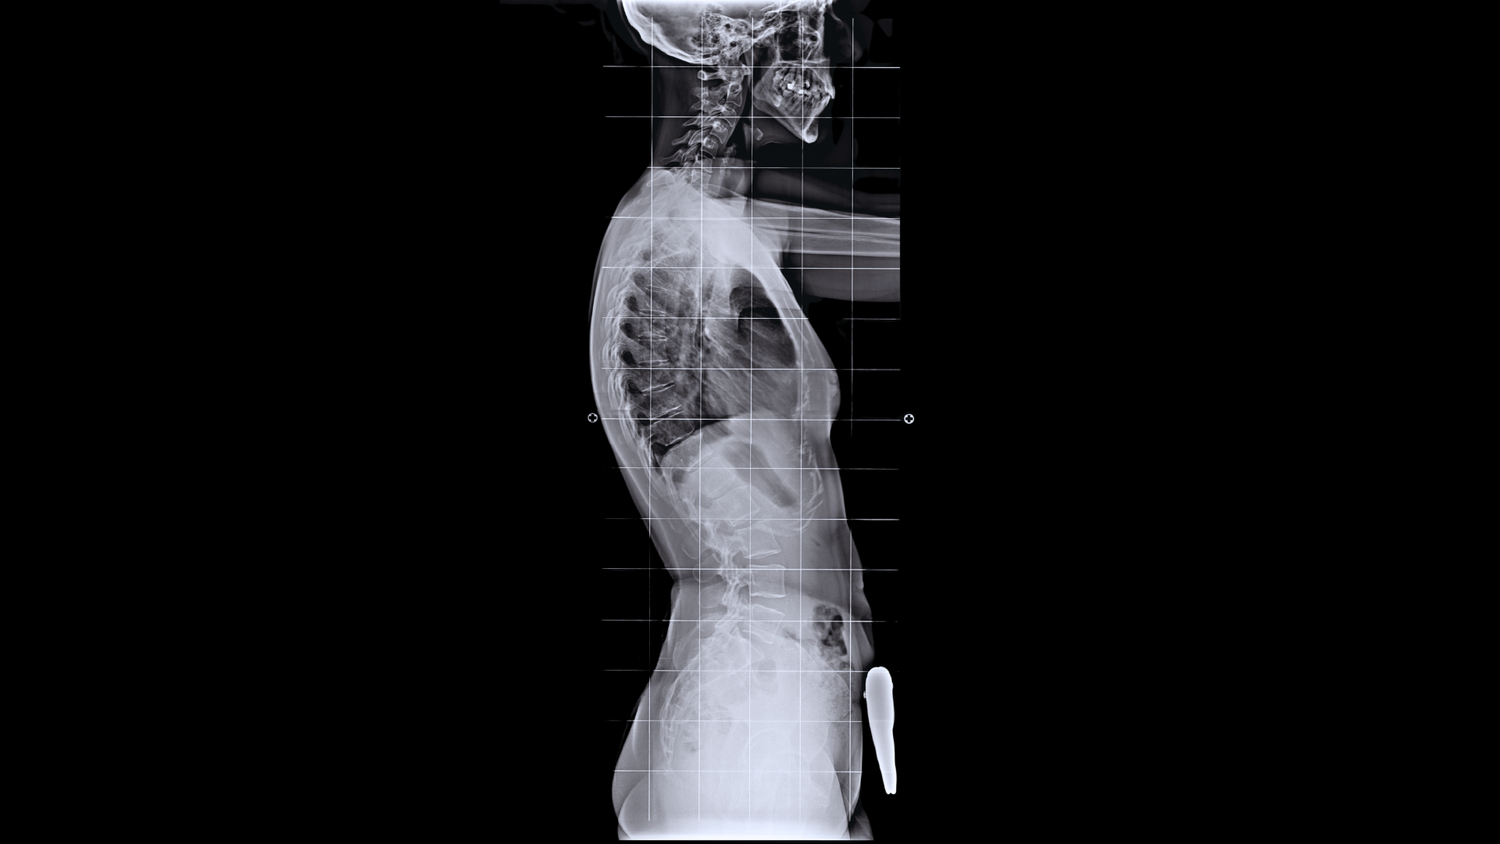

Kyphosis is an excessive outward curvature of the upper spine, leading to a rounded or hunched posture. Some degree of kyphosis is normal, but when the curve becomes too pronounced, it can lead to pain, restricted mobility, and even breathing issues.

Kyphosis affects the thoracic spine (upper back), causing an exaggerated forward curve. Lordosis, on the other hand, refers to excessive inward curvature of the lumbar spine (lower back) or cervical spine (neck). Both conditions impact spinal alignment but in opposite directions.

- Kyphosis – Exaggerated forward curve of the upper back.

- Lordosis – Excessive inward curve in the lower back or neck.

- Scoliosis – A sideways curvature of the spine, often in an “S” or “C” shape.